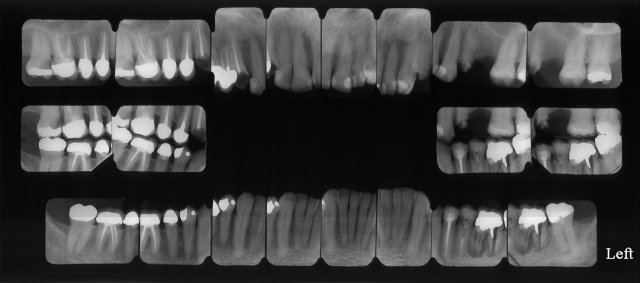

Full Mouth X-Rays

Full Mouth Radiographic Exam

A Full Mouth X-Ray Exam consisting of 20 individual precision X-rays

Can identify dental cavities, short roots, and abnormalities involving the bone adjacent to the teeth.